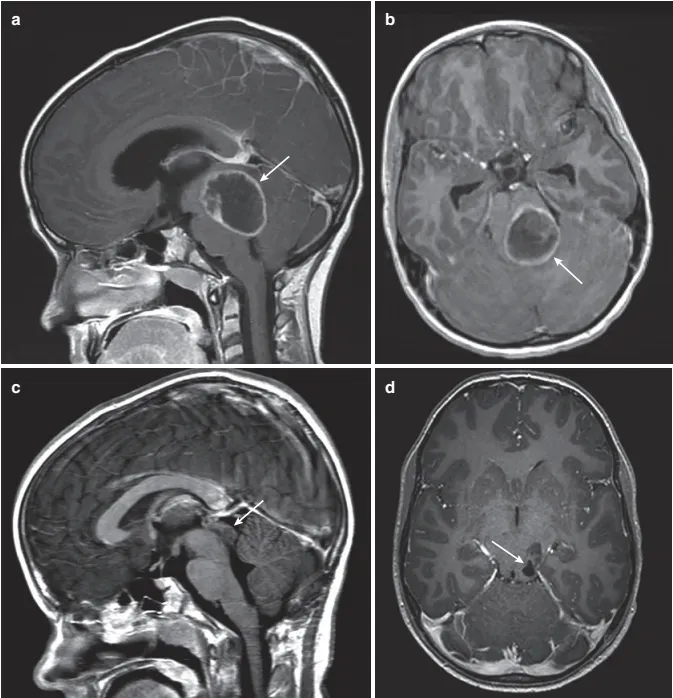

13 岁男孩,巨大非典型顶盖胶质瘤,他患有 1 型神经纤维瘤病NF1,出现头痛和呕吐。(a) 矢状位增强 T1 MRI 显示后颅窝巨大囊性占位性病灶,位于顶盖区中心(箭头)。(b) 轴位 MRI增强MRI 显示顶盖和第四脑室的受累程度(箭头)。(c) 随后进行的后颅窝开颅手术,肿瘤囊肿的引流,并切除囊肿包膜,在这张 T1 加权增强 MRI 扫描中可见顶盖部轻微的变形(箭头)。(d) 术后 T1 加权轴位 增强MRI证实肿瘤起源于顶盖部,肿瘤切除,占位效应解除(箭头)